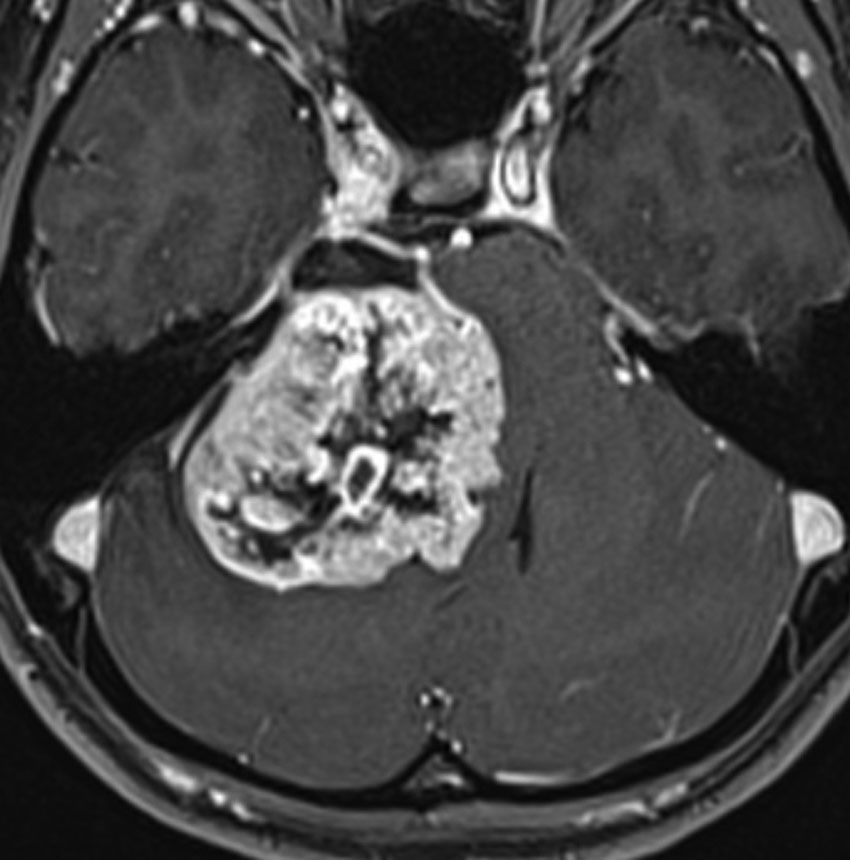

聴神経腫瘍でまず手術が必要なのは巨大なものです。この4枚の写真は私が実際に手術をした患者さんのものです。脳幹部という脳の最も大切なところが腫瘍によって圧迫されて変形しているのが特徴です。右上のものはのう胞性腫瘍なので大きさの割に手術のリスクは高くありませんが,左上のものは実質性で出血性のものですごくリスクが高い手術でした。左下のものは普通のリスク。右下のものは超高難易度のものです。

この腫瘍は脳幹部変形がとても強く,大きいので手術摘出するしか選択肢はありません

- 脳幹部の変形が高度な大きな腫瘍になると手術するしかありません

- 4cmを超えると危険だと考えてください

- のう胞性(腫瘍の内部がほとんど液体)のものは4cmを超えても手術は危なくないです

- 巨大な充実性の聴神経腫瘍の手術では命をなくすリスクもあるものです

- 手術はとても難しいので手術経験の多い脳外科医を捜しましょう

- 大きな腫瘍では無理して全部摘出せず,部分摘出術で小さくしておいてから,手術後に放射線治療をします